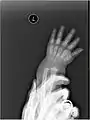

X-ray

X-ray image of right hand with thumb on left.

Multiple fractures of the metacarpals (aka broken hand). (Right hand shown with thumb on left.)

X-ray image of human infant left hand.